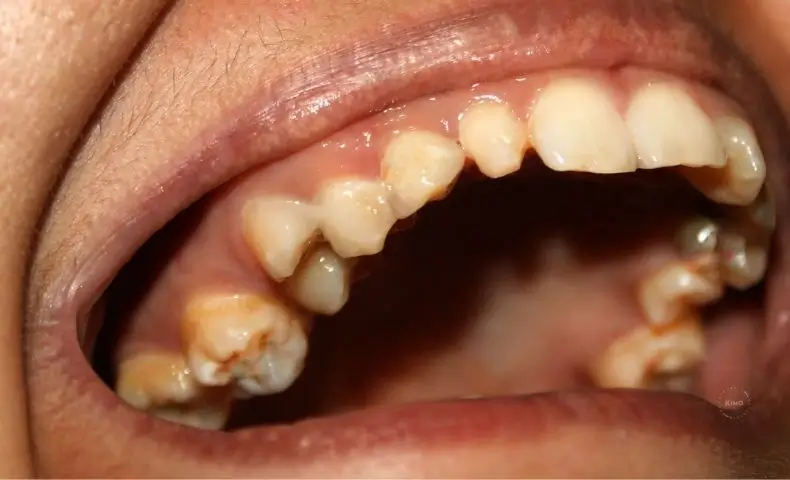

Las obturaciones de amalgama de plata, están formadas por alrededor de un 50% de mercurio , y el otro 50% es una aleación con otros metales como plata, cobre, estaño y zinc. Como explicamos en el post anterior, el mercurio es tóxico y sus vapores también, lo que puede representar un peligro para la salud. Éste, se absorbe y se retiene en órganos como cerebro, riñón, hígado, pulmón y tracto gastrointestinal.